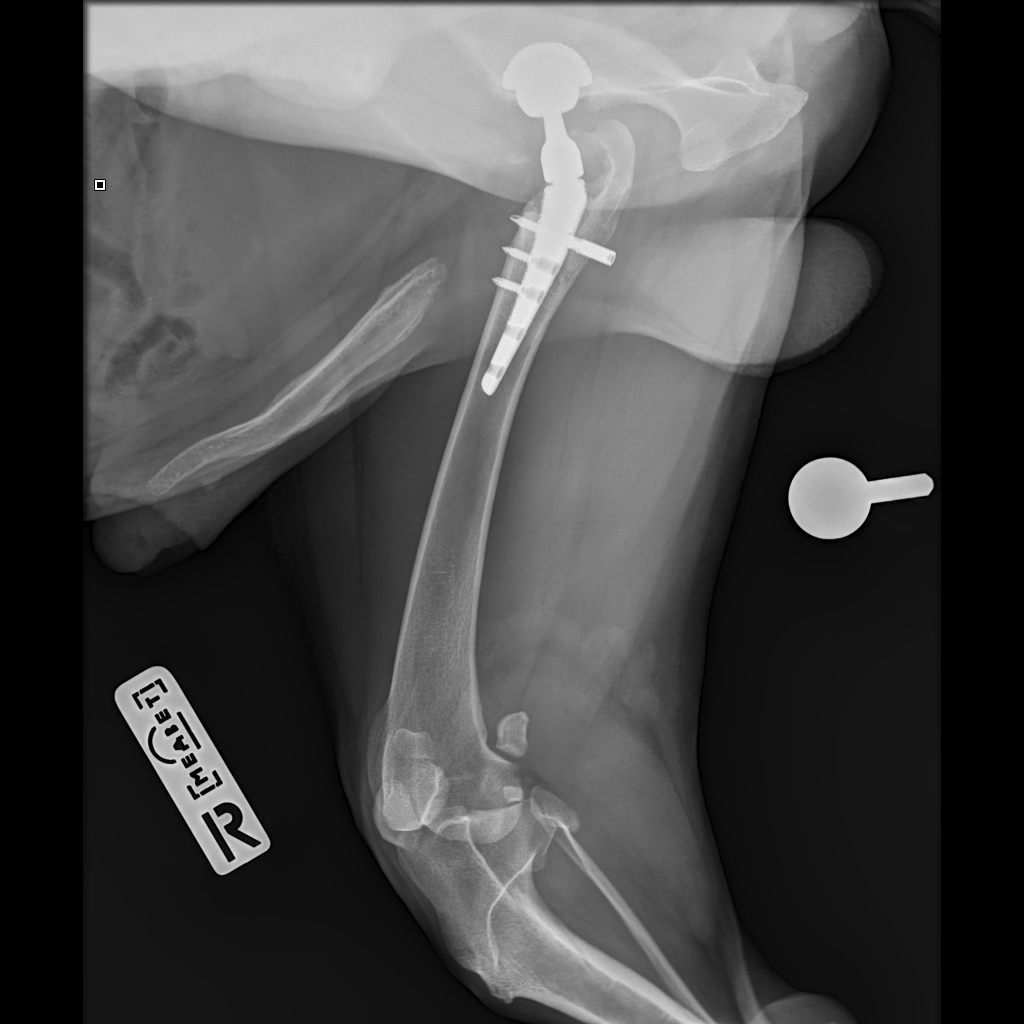

E358D56E-67BF-4D4C-B3F0-BF8F4089D7A2.jpeg

767DD36C-E2E2-41FB-9CCF-6940421D2BB2.jpeg

701487DA-D6D9-4CE0-B18B-EEB120E78EF2.jpeg

Мы ничего не оплачивали. Все включено.

За время противовоспалительной терапии снизилось воспаление и в левом тазобедренном суставе, но увы, форма головки бедренной кости и состояние шейки бедра , лучше не стали:(((

Операция однозначно нужна.

Снимки столь качественные, что их можно в учебник